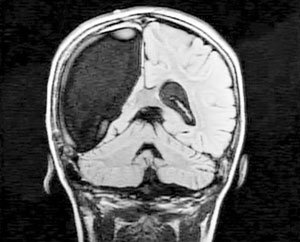

9-летняя жительница Бостона по имени Кэмерон поставила в тупик врачей и ученых. Всего за несколько недель, девочка смогла прийти в себя после сложнейшей операции по удалению правого полушария головного мозга.

В течение долгого времени малышку мучили судороги и тяжелые, едва ли не ежедневные, приступы эпилепсии. В конце концов, врачи вынуждены были удалить ребенку правое полушарие, которое отвечает за чувства, эмоции и ориентацию в пространстве.